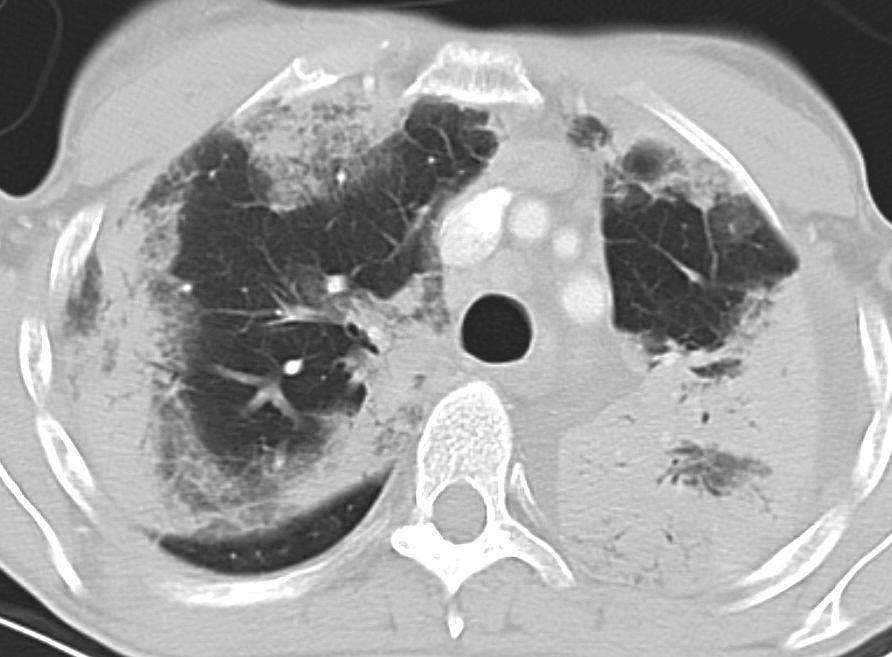

Gallery Pneumonia Eos pneum

Eos pneum